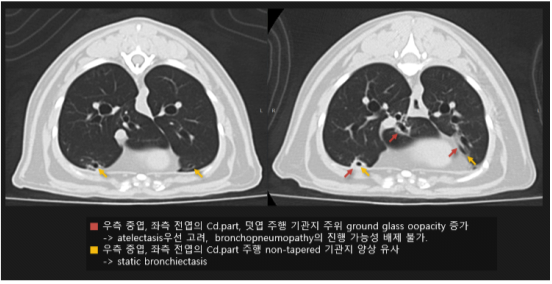

고양이 구강 SCC 방사선치료 후 CT 촬영 결과 1 / 출처: 에스동물암센터

고양이 구강 SCC 방사선치료 후 CT 촬영 결과 2 / 출처: 에스동물암센터

📌방사선 치료 1달 후 결과

기존에 코안에 크게 자리 잡고 있던 종양 덩어리가 눈 주위 뼈, 코뼈 등 광범위하게 퍼져있었습니다. 방사선 치료 1개월 차 CT 촬영 결과, 종양 크기는 줄어 현재 코 안쪽에 1.3cm 정도의 종양만 남이 있는 것으로 확인되었습니다.

다만, 코 안과 부비동에는 여전히 분비물/액체가 차 있는 모습이 보여, 염증(비부비동염)이 남아있을 가능성이 있어 이후 리첵 평가가 추천되었습니다.